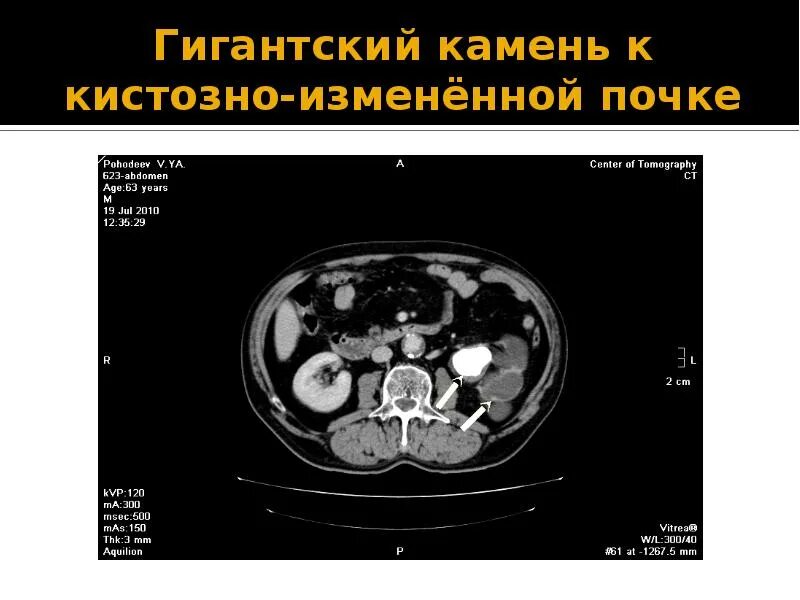

Плотность на кт